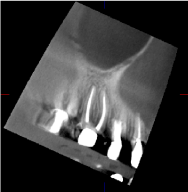

The diagnostic protocol included; auscultation for joint sounds, diagnostic local anesthesia to determine whether the pain was dental or non-dental, and antibiotic regimen to evaluate possible dental infection. None of these tests were diagnostic, according the TMJ specialist. In addition, the TMJ tomography did not reveal any pathologic condition of the condyle, the articular eminence, or any dislocation in an open or closed jaw positions (Figures 2 & 3). The symptoms were alleviated completely after a new occlusal splint with an increased thickness was fabricated and worn by the patient for 48 hours

Figure 3. Right and left TMJ tomography.